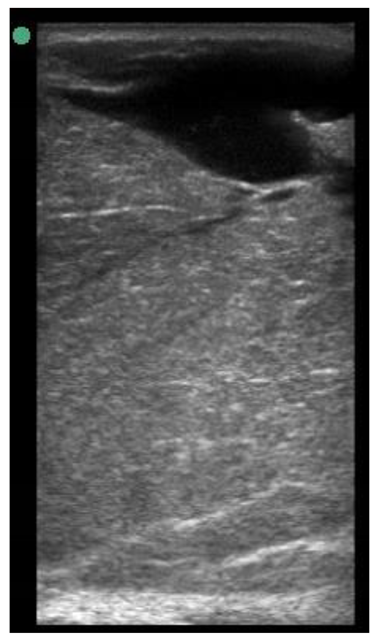

A minimum of three images were taken from each udder half. Images included the gland cistern, mammary parenchyma, putative fat pad and the boundary between the mammary gland and the abdominal wall. One image of suitable resolution per udder half, where all structures were identifiable and present was selected for image processing [27]. Udder halves with an udder palpation score of 4 or 5 (Table 1) at a specific time point (P107, L29 or L100) were considered “abnormal” [23] and were not included in the image selection (heavy: 1 ewe with 1 half and control: 2 ewes with 1 half each).

The image processing was undertaken using ImageJ software [28] as used by Abràmoff et al. [29]. The scales between pixels and millimetres were calculated based on the number of pixels, the scanning depth (mm), and the transducer width (mm) (Figure 4). This method relies on the ability of the operator to interpret and identify lines on the images. To standardize the assessment compartment depth, drawing templates were created for each time point as used by Molenaar et al. [30] and included four representative images from four different yearling ewes with and without the lines drawn for each compartment (Appendix A). The total depth of mammary gland conservative (MTc) was the smallest likely demarcation (abdominal wall) of the mammary gland (Figure 5a), and total depth of the mammary gland generous (MTg) was the largest likely demarcation of the mammary gland visible on the image [30] (Figure 5a). The MTc, MTg, fat pad (FP), parenchyma (PAR), and gland cistern (GC) depths were estimated at the deepest point for each sub-compartment, excluding the skin layers, using the straight tracer (Figure 5a) and were expressed in millimetres.

Figure 5.

(a) Demonstration of delimitations of the mammary total depth conservative (MTc) and generous (MTg), mammary gland cistern (GC), parenchyma (PAR) and the fat pad (FP) and (b) Demonstration of randomly positioning of regions of interest (1, 2, 3) in the parenchyma.

Appendix A. Drawing Templates of Mammary Ultrasound Images in Late Pregnancy, Early Lactation and Weaning in Yearling Ewes

Drawing template of mammary ultrasound images in early lactation (29 days of lactation; L29) in four different yearling ewes.